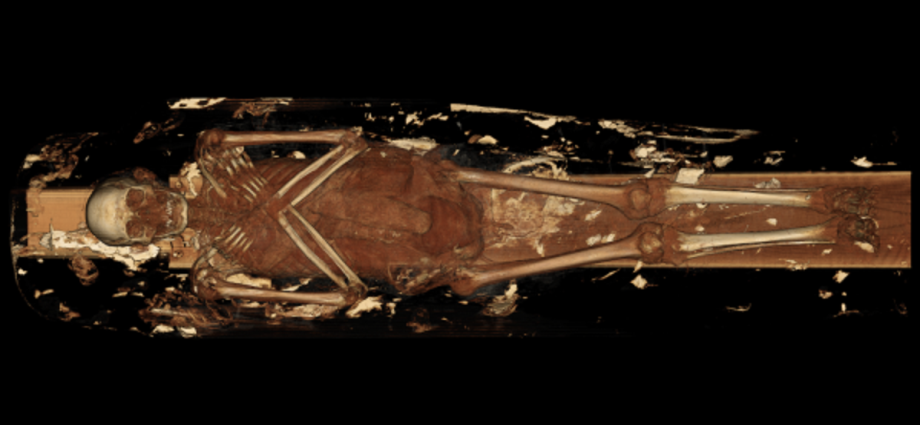

Radiologists subjected two mummies dated to 330BC and 190BC to computed tomography (CT) X-ray scans, offering a view into the lives of ancient Egyptians over 2,000 years ago.

Researchers found that the elder of the two mummies suffered from an aching lower back. The ancient Egyptian was buried with several artefacts, representing several scarab beetles and a fish. Scans revealed his spine had a collapsed lumbar or lower back vertebrae, likely due to natural aging and wear and tear. The other individual appeared to have had dental issues and a severely deteriorated hip, and that he was older at the time of death.

CT scans create hundreds of detailed 3D cross-sectional images, or “slices”, which then experts can digitally “stack” to form digital models.

“These mummies were scanned previously, but due to advancements in scanning technology, the results are much more detailed and extensive than ever before,” said Dr Decker, adding that the new high-resolution images reveal “things that were previously unknown and helped create a picture of what their lives were like”.